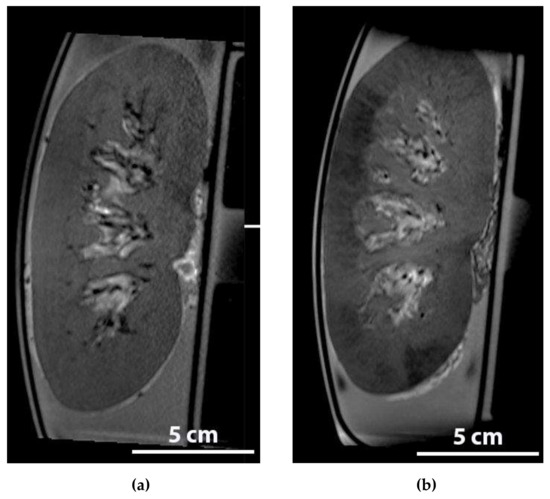

2.6. Detection of Iron Labelled MSCs during NMP in An MRI

4.7. Detection of Iron Labelled MSCs during NMP in An MRI